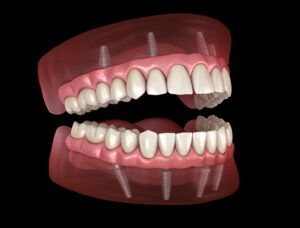

When people have a full arch of severely decayed or infected teeth, then they will want to go get those teeth extracted. After the damaged

When people have a full arch of severely decayed or infected teeth, then they will want to go get those teeth extracted. After the damaged

For those who have traditional dentures, they may be struggling with their unstable and uncomfortable teeth. Traditional dentures only sit on the patient’s gum line,

When people have a full arch of missing teeth, they may be an immediate candidate for full mouth dental implants. But what happens when people

While traditional dentures can be used to replace missing teeth, they can become loose fitting, require messy adhesives, and limit the ability of patients to

The problem with replacing missing teeth with traditional dentures, is that they do not replace the patients missing tooth roots. When missing tooth roots are

Those who have missing teeth may turn to traditional dentures to replace them. While traditional dentures can be effective in restoring people’s ability to smile